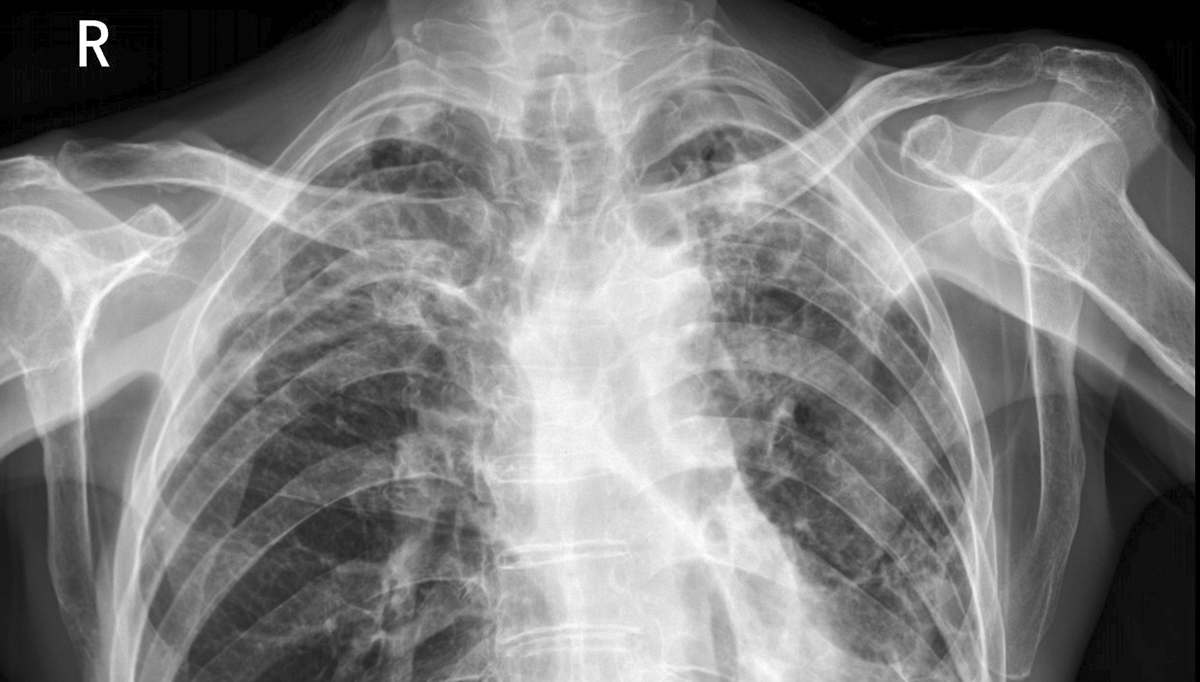

亮度是呈现影像灰阶细节的基础。医学影像中的微小病灶,如乳腺微钙化点、肺部小结节等,往往依赖细微的灰阶差异来识别,而亮度直接影响人眼对灰阶的分辨能力。研究表明,亮度越高,可辨识的灰阶层次越丰富,当医用诊断显示器亮度从 1000cd/m² 降至 800cd/m² 时,低对比度区域的可见性会显著降低,可能直接掩盖关键病灶。按照 DICOM PS3.14 标准,医用诊断显示器需精准匹配灰阶标准显示函数,而稳定的亮度正是实现这一匹配的核心保障。

亮度稳定性关乎诊断一致性与准确性。医用诊断显示器长期使用后易出现亮度衰减,若未及时校准,可能导致灰阶曲线偏移,偏离 DICOM 标准。数据显示,亮度衰减 5% 就会使肺部结节漏诊率上升 12%,在乳腺钼靶、CT 等低对比度影像诊断中影响更为显著。同时,医院阅片环境存在环境光干扰,充足的亮度能有效抵消环境光影响,避免影像细节被 “洗掉”,这也是医用诊断显示器需维持≥500 cd/m² 环境光补偿亮度的原因。